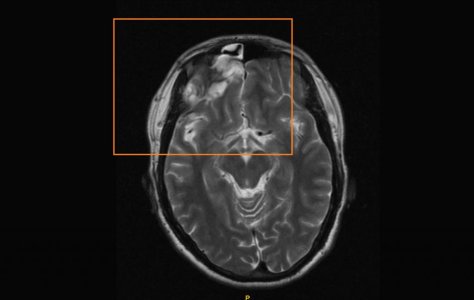

В 2012 году перенес ушиб головного мозга средней степени (на МРТ осталась зона кистозно-глиозных изменений в лобной доле). В течение полутора лет после травмы ничего не беспокоило. Однако спустя полтора года, летом 2013 года, появился симптом - постоянная тяжесть в голове, - который не проходит по сей день, значительно снижая качество жизни.

1. Очаги глиоза.

2. Ассиметрия кровотока по венозным синусам.

Врач нейрохирург сказал, что по сей день не рассосалась кровь (оставшаяся от гематомы после травмы) - видимо, из-за нарушенного венозного оттока, так как снижен уровень метаболизма между клетками мозга в силу застоя крови. Скажите, пожалуйста, есть ли изменения на МРТ в динамике - действительно ли появилось что-то новое на снимках? Действительно ли есть негативная динамика? Или, напротив, что-то рассосалось и динамика положительная? И как мне скоординировать лечение, чтобы избавиться от симптомов?

В 2012 году перенес ушиб головного мозга средней степени (на МРТ осталась зона кистозно-глиозных изменений в лобной доле). В течение полутора лет после травмы ничего не беспокоило. Однако спустя полтора года, летом 2013 года, появился симптом - постоянная тяжесть в голове, - который не проходит по сей день, значительно снижая качество жизни.

1. Очаги глиоза.

2. Ассиметрия кровотока по венозным синусам.

Врач нейрохирург сказал, что по сей день не рассосалась кровь (оставшаяся от гематомы после травмы) - видимо, из-за нарушенного венозного оттока, так как снижен уровень метаболизма между клетками мозга в силу застоя крови. Скажите, пожалуйста, есть ли изменения на МРТ в динамике - действительно ли появилось что-то новое на снимках? Действительно ли есть негативная динамика? Или, напротив, что-то рассосалось и динамика положительная? И как мне скоординировать лечение, чтобы избавиться от симптомов?